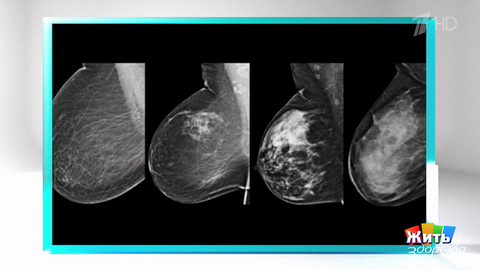

Анализ риска рака груди: что делать дальше? Фрагмент

Анализ, который предскажет риск рака груди. Кому необходимо его сдать? И что делать, если результат положительный — подробный разбор скрининга, его точности и дальнейших шагов.